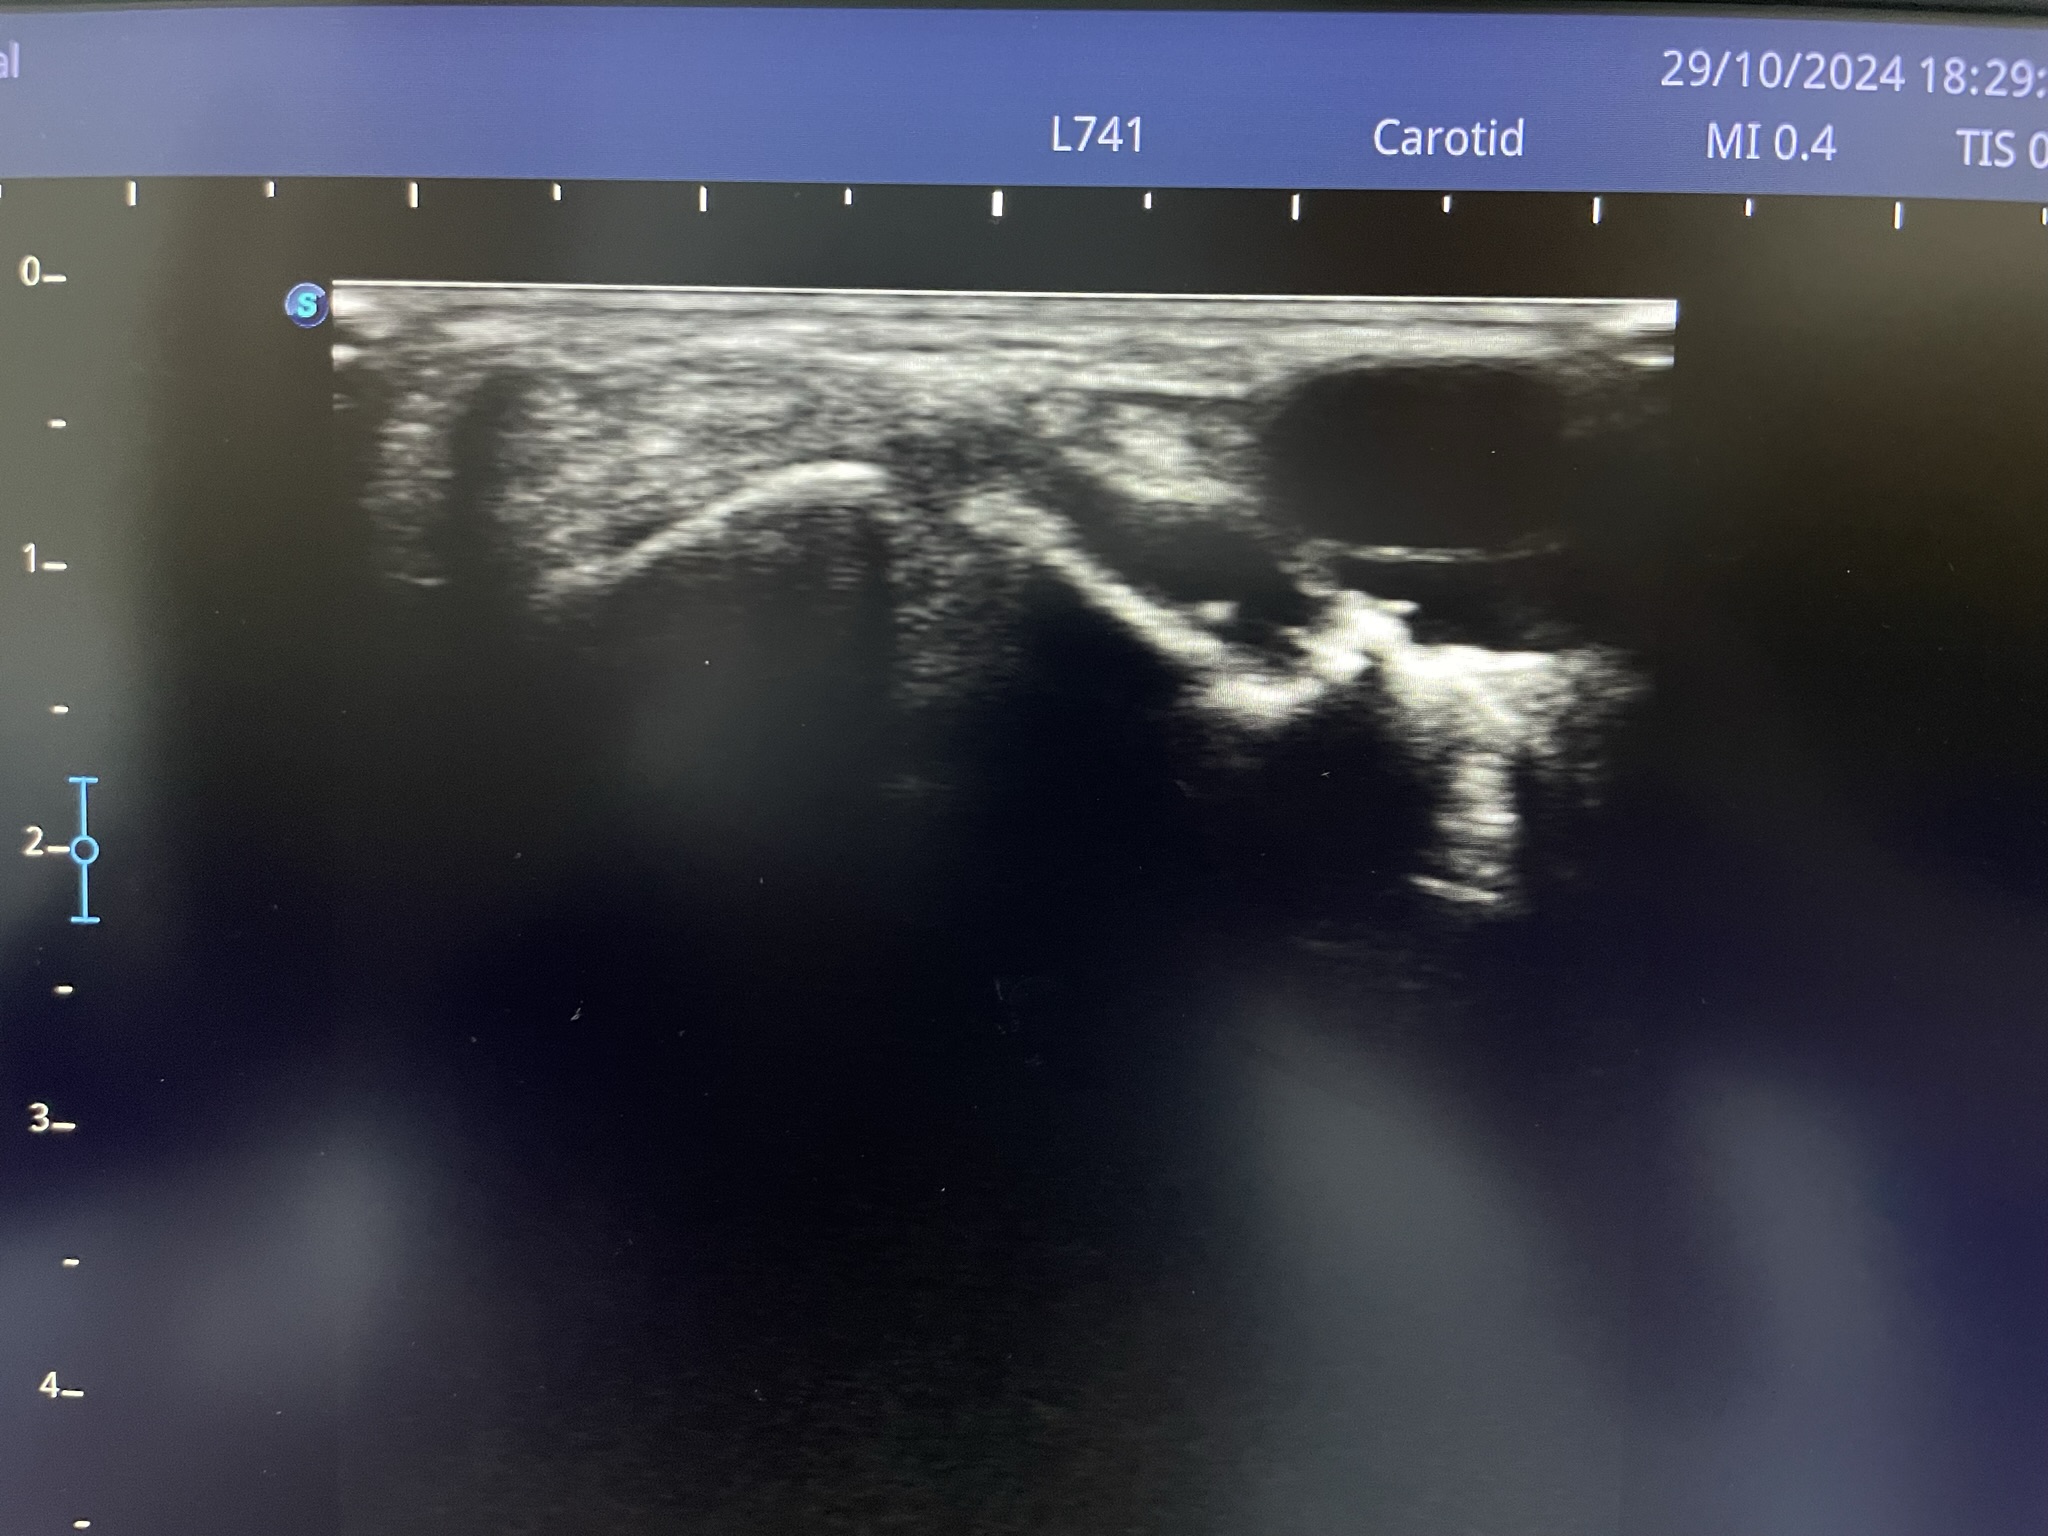

Клинический случай: тыльная гигрома запястья

Пациент с тыльной гигромой, подтверждённой на УЗИ. Выполнено хирургическое лечение, документированы этапы контроля и результаты.